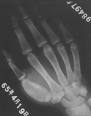

X線平片表現為骨膜增生及新骨形成,同時髓腔逐漸擴大,骨皮質膨脹變薄,可有死骨形成。但在老年患者新生骨多不明顯,有時可出現病理性骨折。一般勿需行CT及MRI檢查。